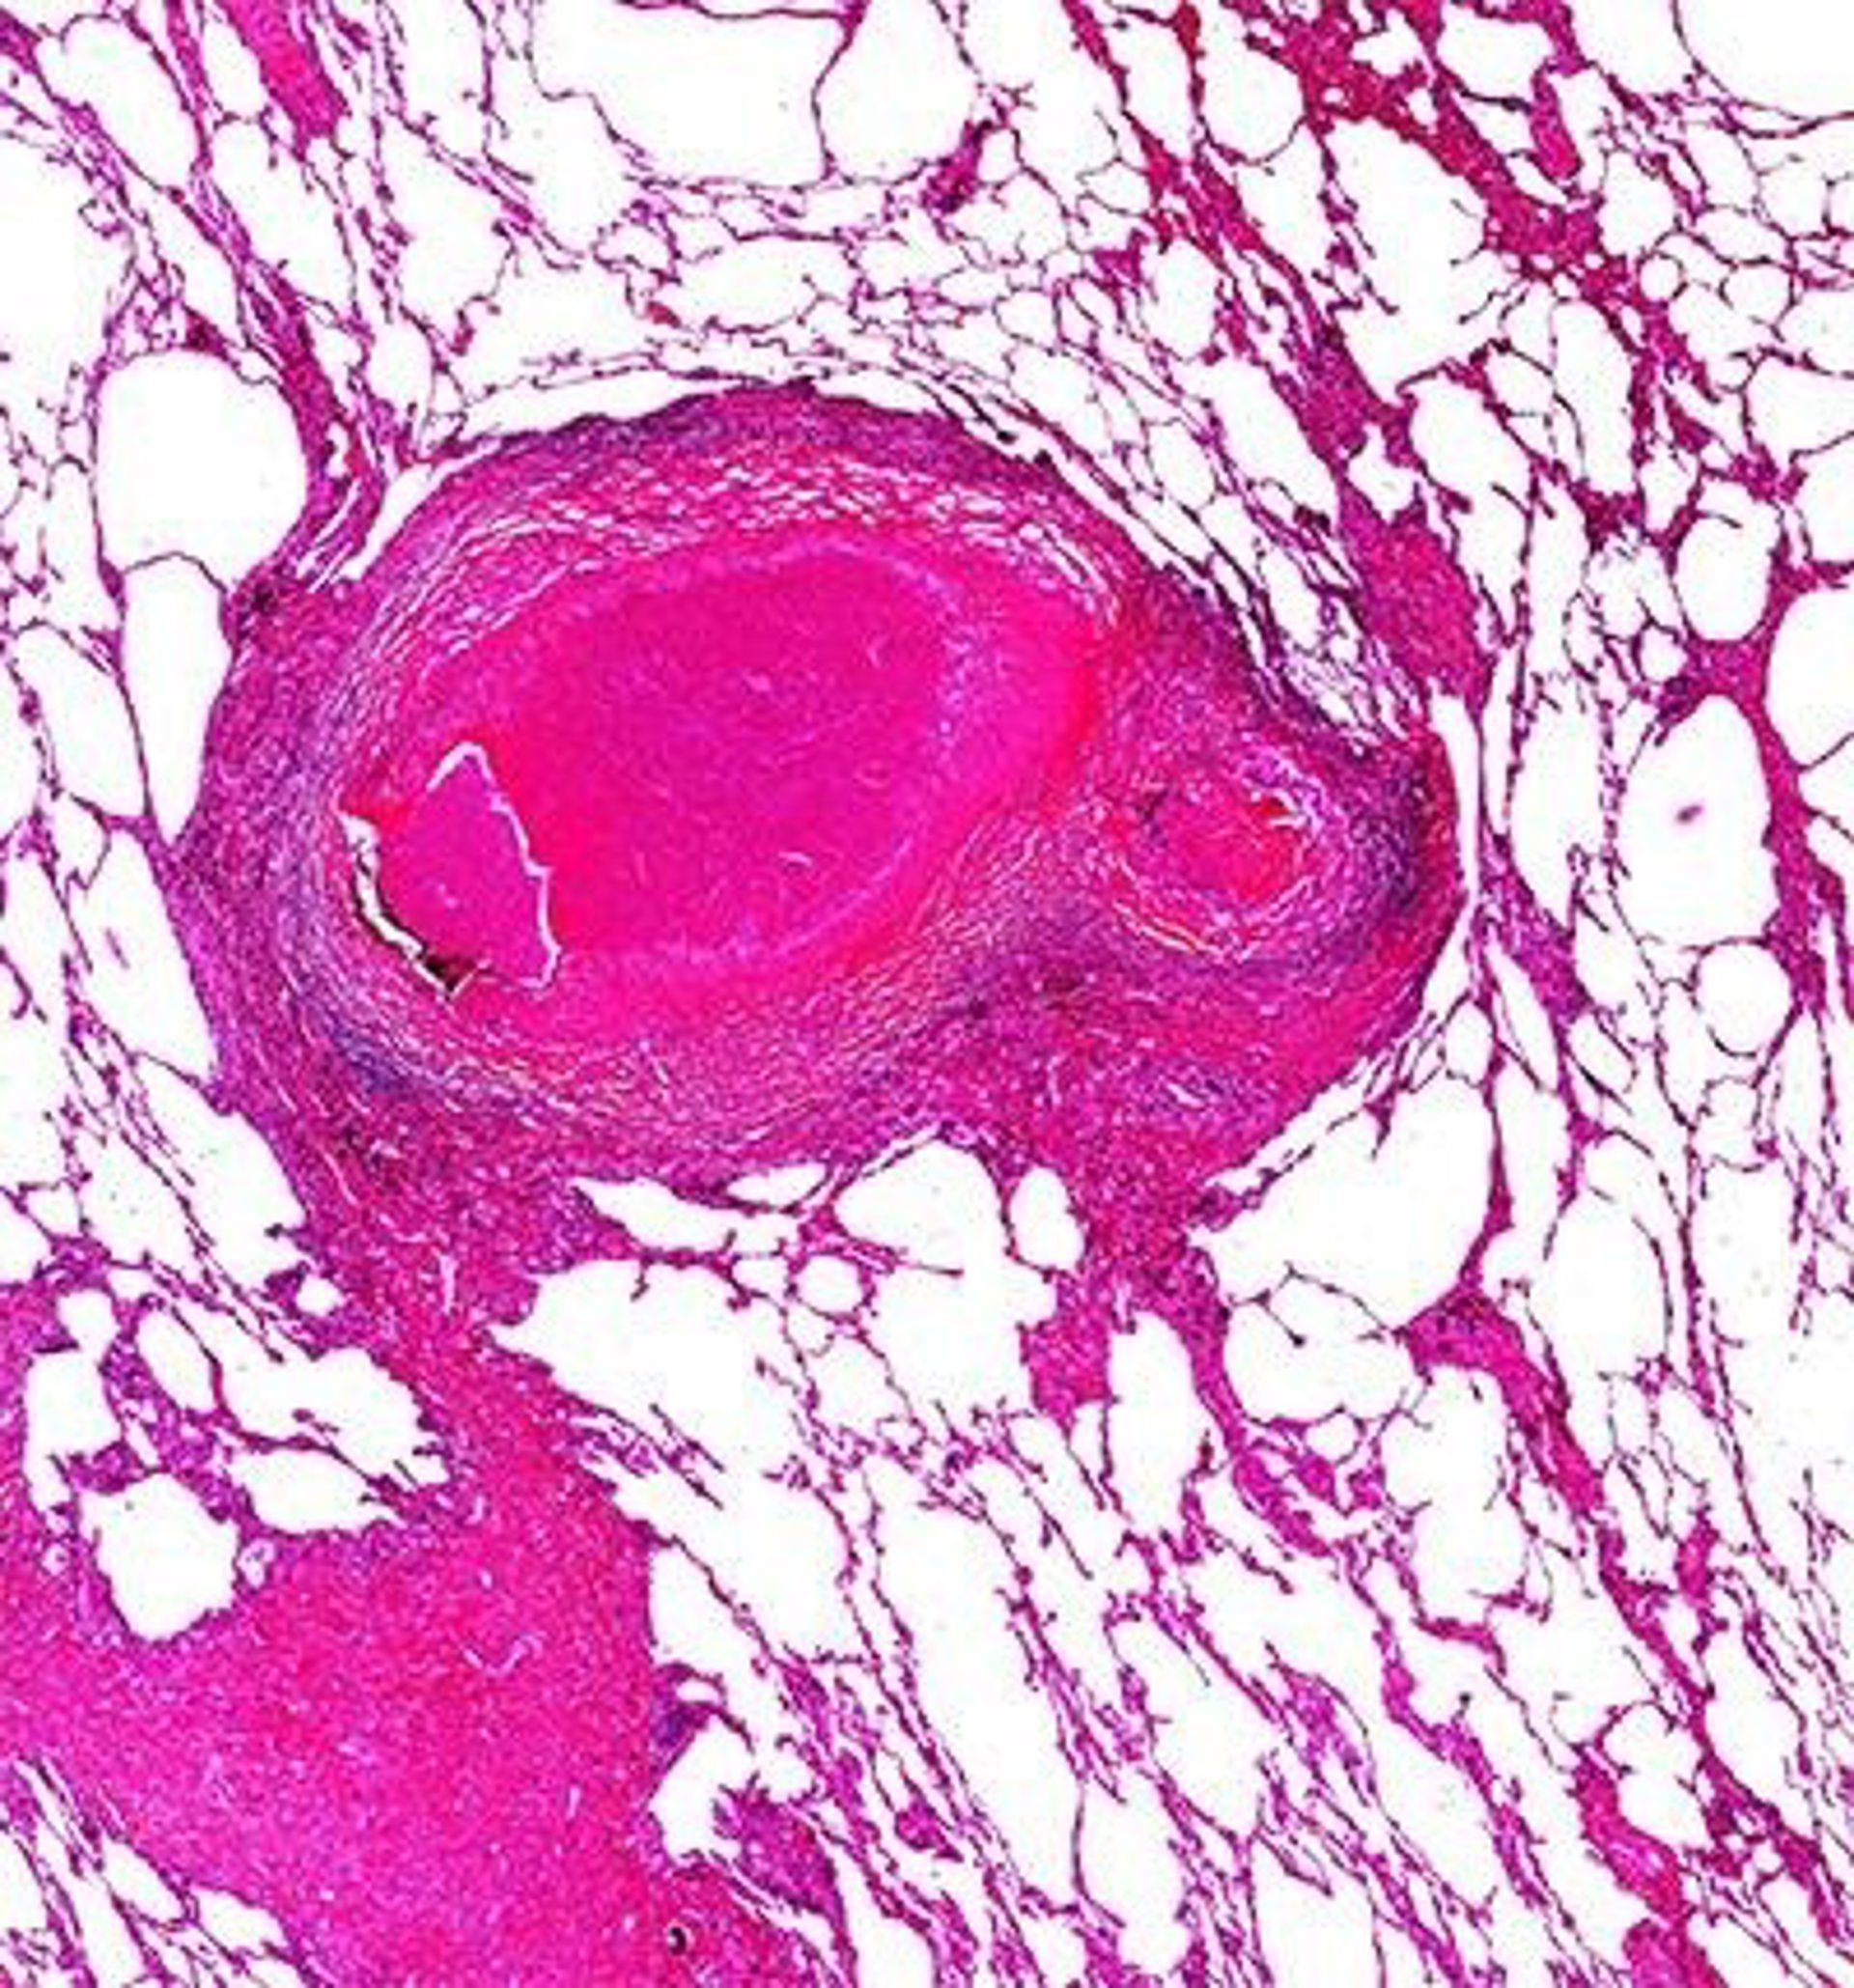

Investigadores de la Unidad de Tuberculosis Experimental del Institut de Recerca Germans Trias i Pujol (IGTP) han publicado los primeros resultados de un modelo computacional que pretende reproducir la dinámica de las lesiones por tuberculosis en un pulmón virtual.

El modelo describe "el crecimiento, la fusión y la proliferación" de lesiones de tuberculosis en un árbol bronquial computacional, construido con a partir de un algoritmo iterativo, ha informado el instituto en un comunicado este viernes.

Permite reproducir y entender los datos experimentales, además de mostrar "una importante relación" entre el número final de lesiones por tuberculosis con la frecuencia de reinfección y el crecimiento de los daños.